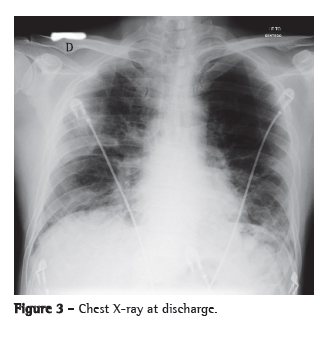

A chest X-ray showed worsening of the bilateral alveolar infiltrate, and a chest CT scan showed multifocal ground-glass infiltrate (Figures 1 and 2).

The patient was admitted to the ICU and treated with oseltamivir, ceftriaxone, azithromycin and a corticosteroid. He received ventilatory support with intermittent positive pressure breathing, which was maintained at 50% via a Venturi mask, at a resting SpO2 of 92%. The patient progressively improved and was discharged from the ICU ten days later, presenting an SpO2 of 94% on room air, together with radiological improvement (Figure 3). He developed no fever or hemodynamic instability during the hospital stay.

The most common radiological manifestations of influenza pneumonia consist of reticulonodular opacities, with or without superimposed areas of consolidation. Less commonly, patients with influenza pneumonia can present with focal areas of consolidation, typically in the lower lobes, without apparent reticular or reticulonodular opacities. The radiological abnormalities typically resolve in approximately three weeks. Consolidations can occur due to secondary bacterial pneumonia.(7,8)

On chest CT scans, various patterns are possible. However, the ones most commonly reported are those showing lobular areas, typically bilateral, of ground-glass attenuation. Other possible patterns are the presence of focal areas of consolidation, centrilobular nodules and the tree-in-bud pattern.(9)